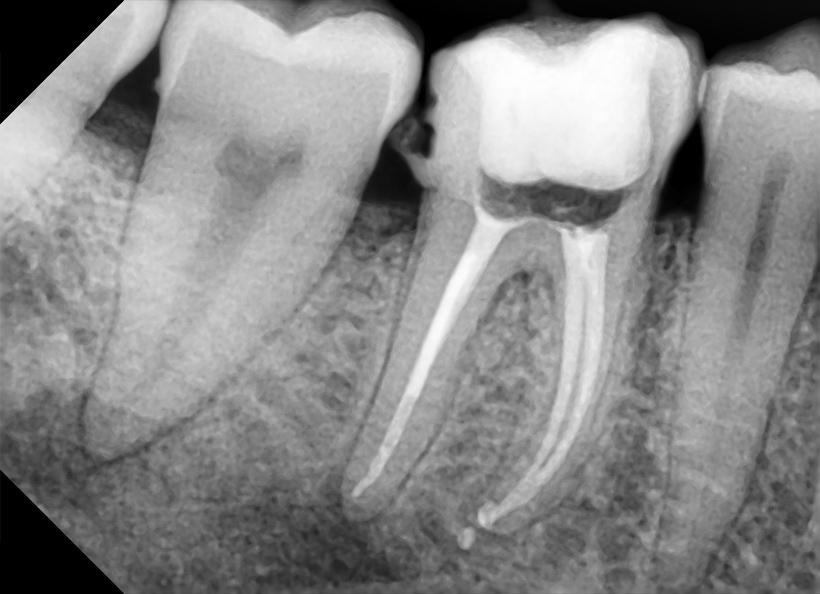

RX Retro Alveolară

Radiografia retroalveolară este o investigație de detaliu, esențială pentru vizualizarea unuia sau a mai multor dinți în întregime, de la coroană până la vârful rădăcinii.

50 RON